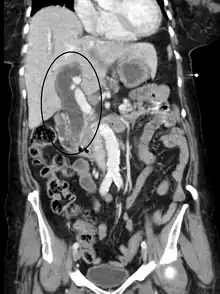

Posthepatic causes (Obstructive jaundice)

Posthepatic jaundice (obstructive jaundice) is caused by a blockage of bile ducts that transport bile containing conjugated bilirubin out of the liver for excretion.[29] This is a list of conditions that can cause posthepatic jaundice:

- Choledocholithiasis (common bile duct gallstones). It is the most common cause of obstructive jaundice.

- Pancreatic cancer of the pancreatic head